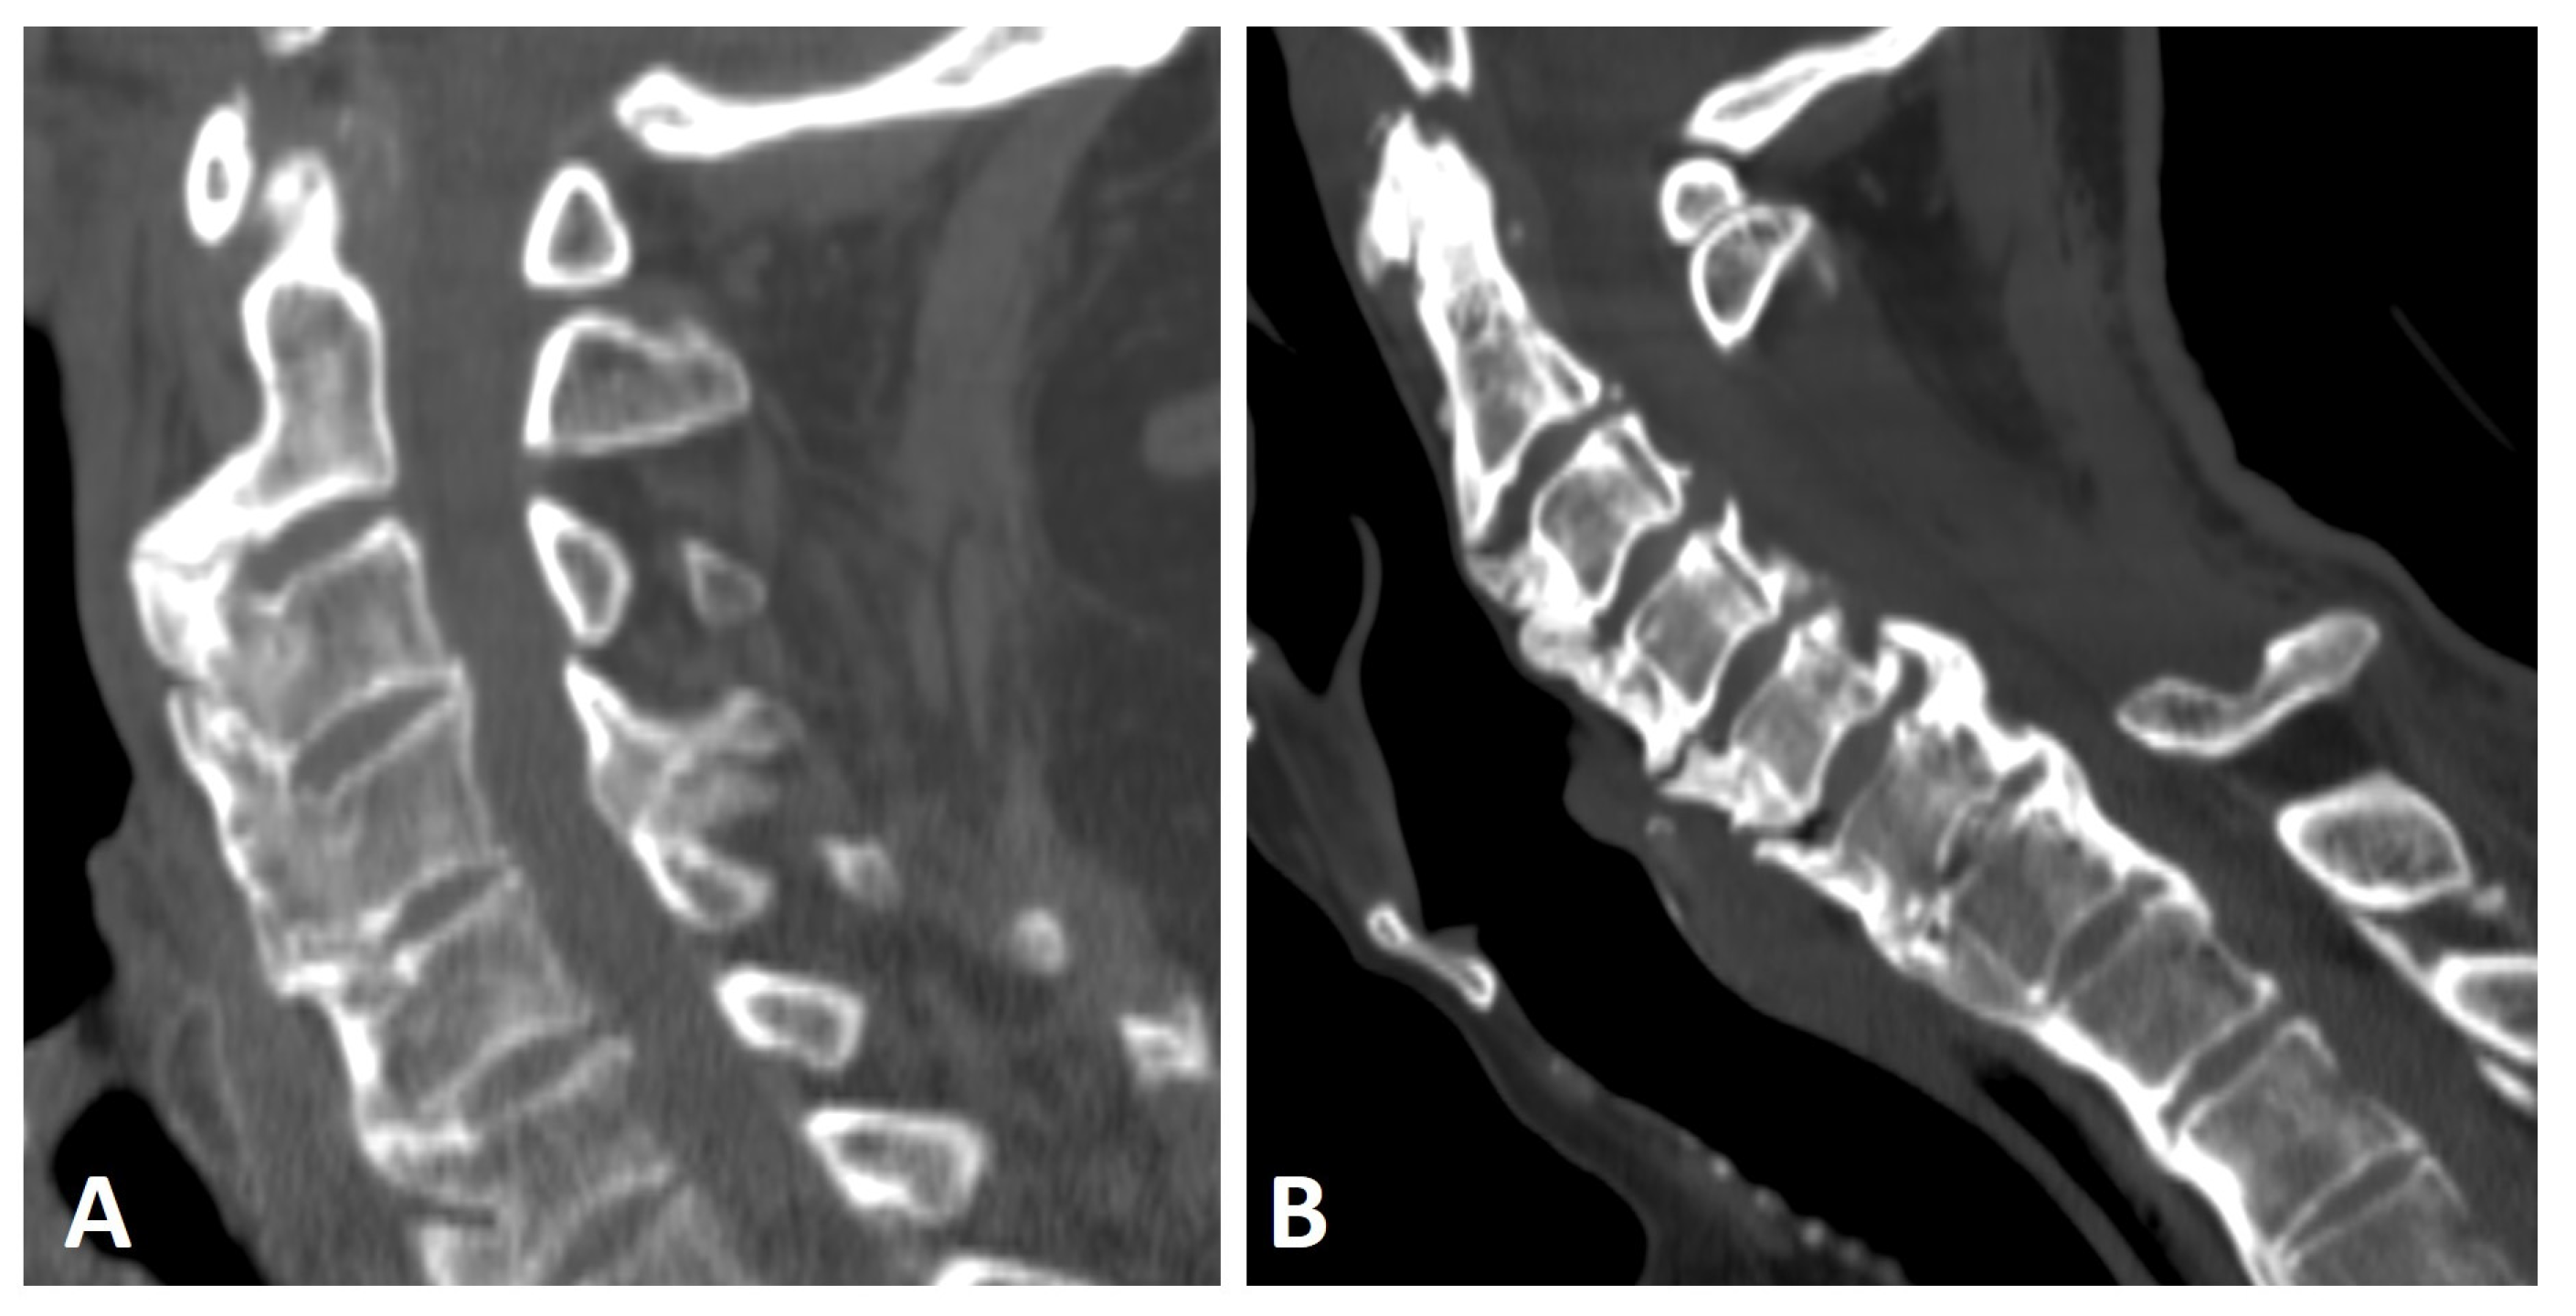

Figure 2.

Sagittal CT reconstruction images of two patients with thoracic (not shown) and cervical DISH. (A) Flowing chunky osteophytes are located anteriorly to the vertebrae, forming a “candle flame” or “parrot-beak” image. (B) Thick, not-yet-flowing anterior osteophytes and thick posterior osteophytes at the C5–6 level.